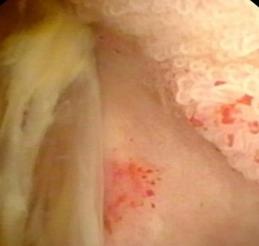

• 内镜诊断和治疗十二指肠黏膜下恒径动脉破裂出血并活动性出血的价值(附6例报告)

2026, 32(1):80-83. DOI: 10.12235/E20250357

摘要 (39) HTML (37) PDF 1.21 M (63) 评论 (0) 收藏

摘要:目的 探讨内镜诊断和治疗十二指肠黏膜下恒径动脉破裂出血并活动性出血的价值。方法 回顾性分析2015年6月-2023年1月该院经内镜确诊十二指肠黏膜下恒径动脉破裂出血并活动性出血的6例患者的临床资料。总结临床表现、内镜下特征和治疗转归。结果 于24 h内完成急诊内镜检查,证实6例均为单纯十二指肠黏膜下恒径动脉破裂出血,并成功行内镜下钛夹止血治疗。结论 内镜诊断十二指肠黏膜下恒径动脉破裂出血所致的大出血,具有较高的价值。此外,于内镜下及时采取积极、有效的干预措施,可快速止血,降低死亡率。值得应用于临床。